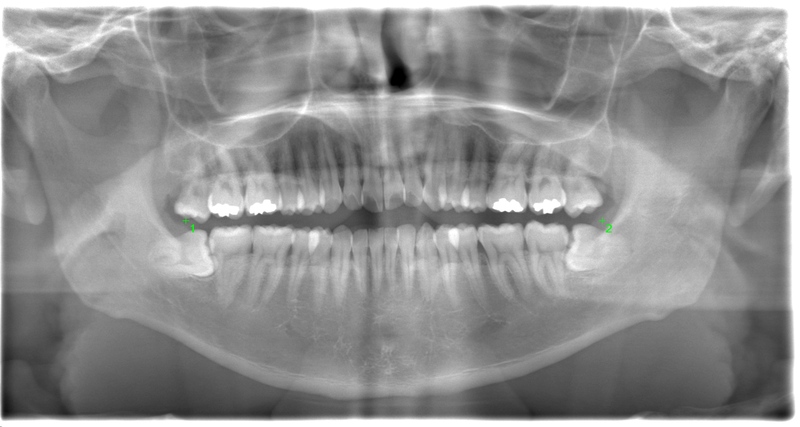

CASE 1

基本情報

| 年齢・性別 | 30代・女性 |

| 主訴 | 左右に分けて親知らずを抜きたい、できれば痛くなく抜きたい |

| 親知らずのはえ方 | 完全に出ていてまっすぐはえている |

| 抜歯期間 | 15分 |

| 抜歯費用 | 約2,000円(保険内) |

| 抜歯内容 |

何度か虫歯になり痛みはないが早めに抜きたい。 完全に頭が出ているため歯ぐきを切ったり骨を削らずに抜歯しました。 根の形も単純なため抜歯自体は5分もかからず上下ともに終わりました。 術後痛みや腫れも出ていません。 抜歯後は感染をしやすいため必ず抗生物質を飲み切ってください。 |